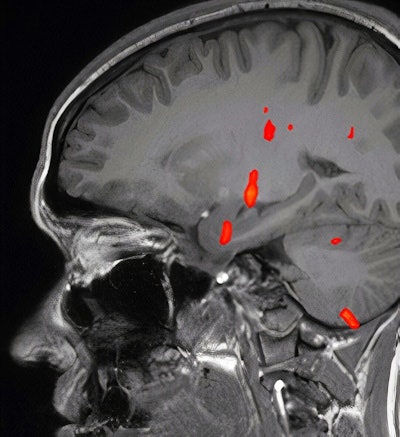

Fused Blood oxygenation level-dependent (BOLD) map on sagittal T1-weighted image shows activation at the level of anteromedial temporal lobe, thalamus, and other regions, but absent activation of the orbitofrontal cortex. Images courtesy of Dr. Khaled Gad, PhD.Problems with smell and taste are common in patients with COVID-19, occurring in an estimated 52.7% and 43.9% with the virus, respectively, according to one meta-analysis, the authors noted.

Blood oxygenation level-dependent (BOLD) activation on fMRI studies has been associated with olfactory sensation, a complex activity in the brain that involves the amygdala, the orbitofrontal cortex, and other structures, Gad and Ismail wrote.

"There is accumulating evidence of implication of OFC in patients with COVID-19 with olfactory dysfunction," they noted.

Fused BOLD and fractional anisotropy map on coronal T1-weighted image shows activation of the right uncus/piriform cortex with intact, symmetric architecture of surrounding white-matter tracts.The patient in the case report experienced taste and smell dysfunction for three months and had been referred to a neurology clinic, where she had a normal examination. Clinicians performed a task-based functional MRI study that involved exposure to smells and the generation of BOLD activation maps. Activation was not seen in the orbitofrontal cortex, while there was a strong BOLD signal in the right uncus/piriform cortex, they reported.

"The utility of fMRI in patients with COVID-19 is not well established, and to our knowledge this is the first published report using fMRI in a patient with persistent cacosmia and cacogeusia after COVID-19 infection," they wrote. "Given these findings, we could suggest central olfactory pathway impairment, mainly involving OFC, may be involved in the underlying etiology of persistence of olfactory and gustatory symptoms in patients after COVID-19 infection."